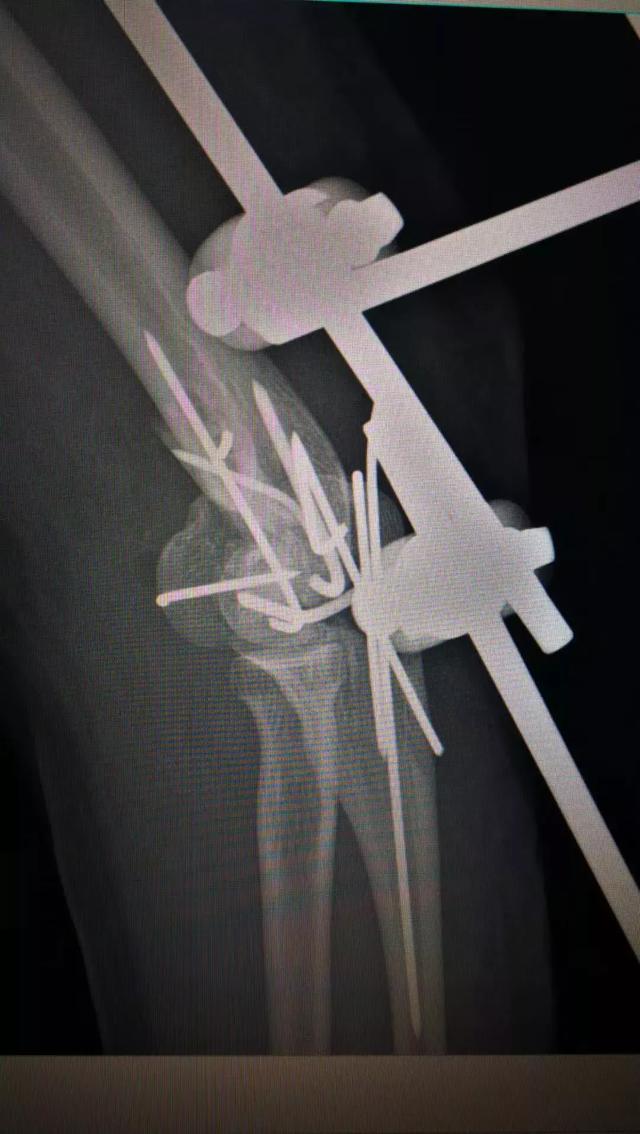

于是,张主任带领团队凌晨急诊给她做了肘部扩创、血管神经肌腱关节囊探查修复、局部皮瓣转移、肱骨骨折尺骨骨折切开复位内固定+骨折外固定关节外固定架固定、食指近节指骨骨折內固定术。此类手术需要医生极为细致与耐心,还要在术中不断地评估决策,为伤员的短期与长期利益抉择出最佳方案。

.术前术后对比图